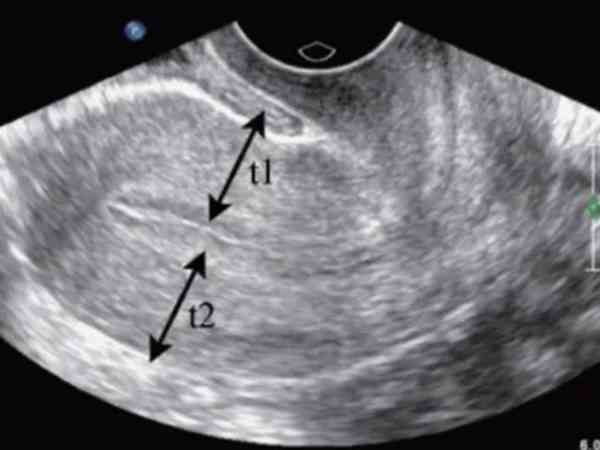

宫腔镜检查是诊断宫内异常的金标准,可以在直视下了解宫腔环境,观察有无宫腔粘连、子宫纵隔、内膜息肉、粘膜下肌瘤、剖宫产瘢痕憩室、子宫内膜炎等可能影响胚胎移植成功率的疾病,可以大大提高试管的移植成功率,避免过多的重复治疗,减少对宫腔的刺激。

多次刮宫、自然流产后,可能存在导致子宫内膜损伤、粘连等问题的姐妹在移植前需要进行宫腔镜检查,以评估子宫状态。通常胚胎移植 3 次及以上均失败的患者,通过宫腔镜检查可排除 B 超难以发现的子宫内膜问题,如轻微的炎症、局部血流异常等,还可通过轻度搔刮内膜的方式,改善子宫环境,增加胚胎着床的几率。